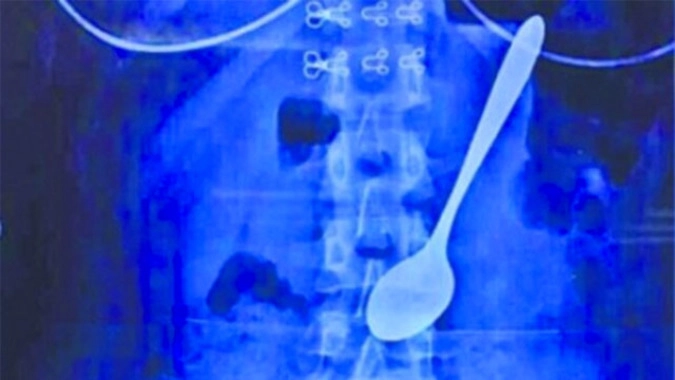

Хирурги извлекли из желудка девушки металлическую ложку

Студентка университета в китайском городе Ухань оказалась на больничной койке после того, как случайно проглотила ложку.

22-летняя девушка ела мороженое на ходу, направляясь к общежитию. Неожиданно ее толкнули в спину, от испуга она вскрикнула и проглотила 14-сантиметровую металлическую ложку.

Чуть позже медикам все же удалось объяснить студентке, к каким последствиям может привести 14-сантиметровая металлическая ложка в желудке.

Чтобы извлечь инородный предмет хирурги придумали прикрепить к мединструменту рыболовную снасть, с помощью которой спустя 19 минут достали ложку, пишет The Shanghaiist.